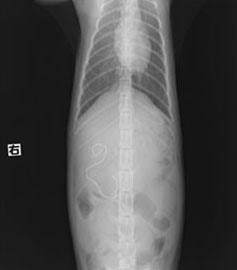

・レントゲン検査:腸内ガス陰影重度

・バリウム像影検査:造影後2時間、胃からのバリウム排泄なし上記検査結果より、内視鏡検査実施。

・内視鏡検査結果:胃内炎症性病変あり。胃の幽門部から十二指腸領域に向かいヒモ状異物確認。

内視鏡検査結果より、十二指腸領域へのヒモ状異物の可能性があるため、同日腸内異物摘出術実施。

腸内異物摘出術

腸管のアコーディオン様所見

腸内異物摘出

摘出した異物

今回の様なヒモ状の異物は、腸の蠕動運動により腸管を傷つけ、発見が遅れると腸穿孔などの重篤な状態を引き起こします。本症例は、術後1週間程で回復し、現在の経過は良好です。